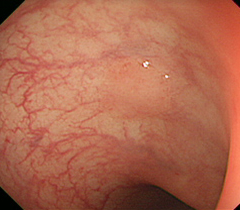

NBI(狭帯域光観察)とは、2つの短い波長の特殊光(狭帯域光)を使うことにより、粘膜の微細な表面構造や毛細血管をくっきりと写し出すという技術です。

がんやポリープ等の腫瘍は、周囲の粘膜とは表面の構造、毛細血管が違っているので異なる色調で表示され腫瘍が浮かび上がって見え、より小さな病変でも見落とさずに発見することができます。

特にこれまで通常の内視鏡検査では発見が困難であった食道がんや咽頭、喉頭のがんの発見精度が大幅に向上しました。当院で導入している最新のNBIシステムでは、従来以上の明るさで観察が可能です。